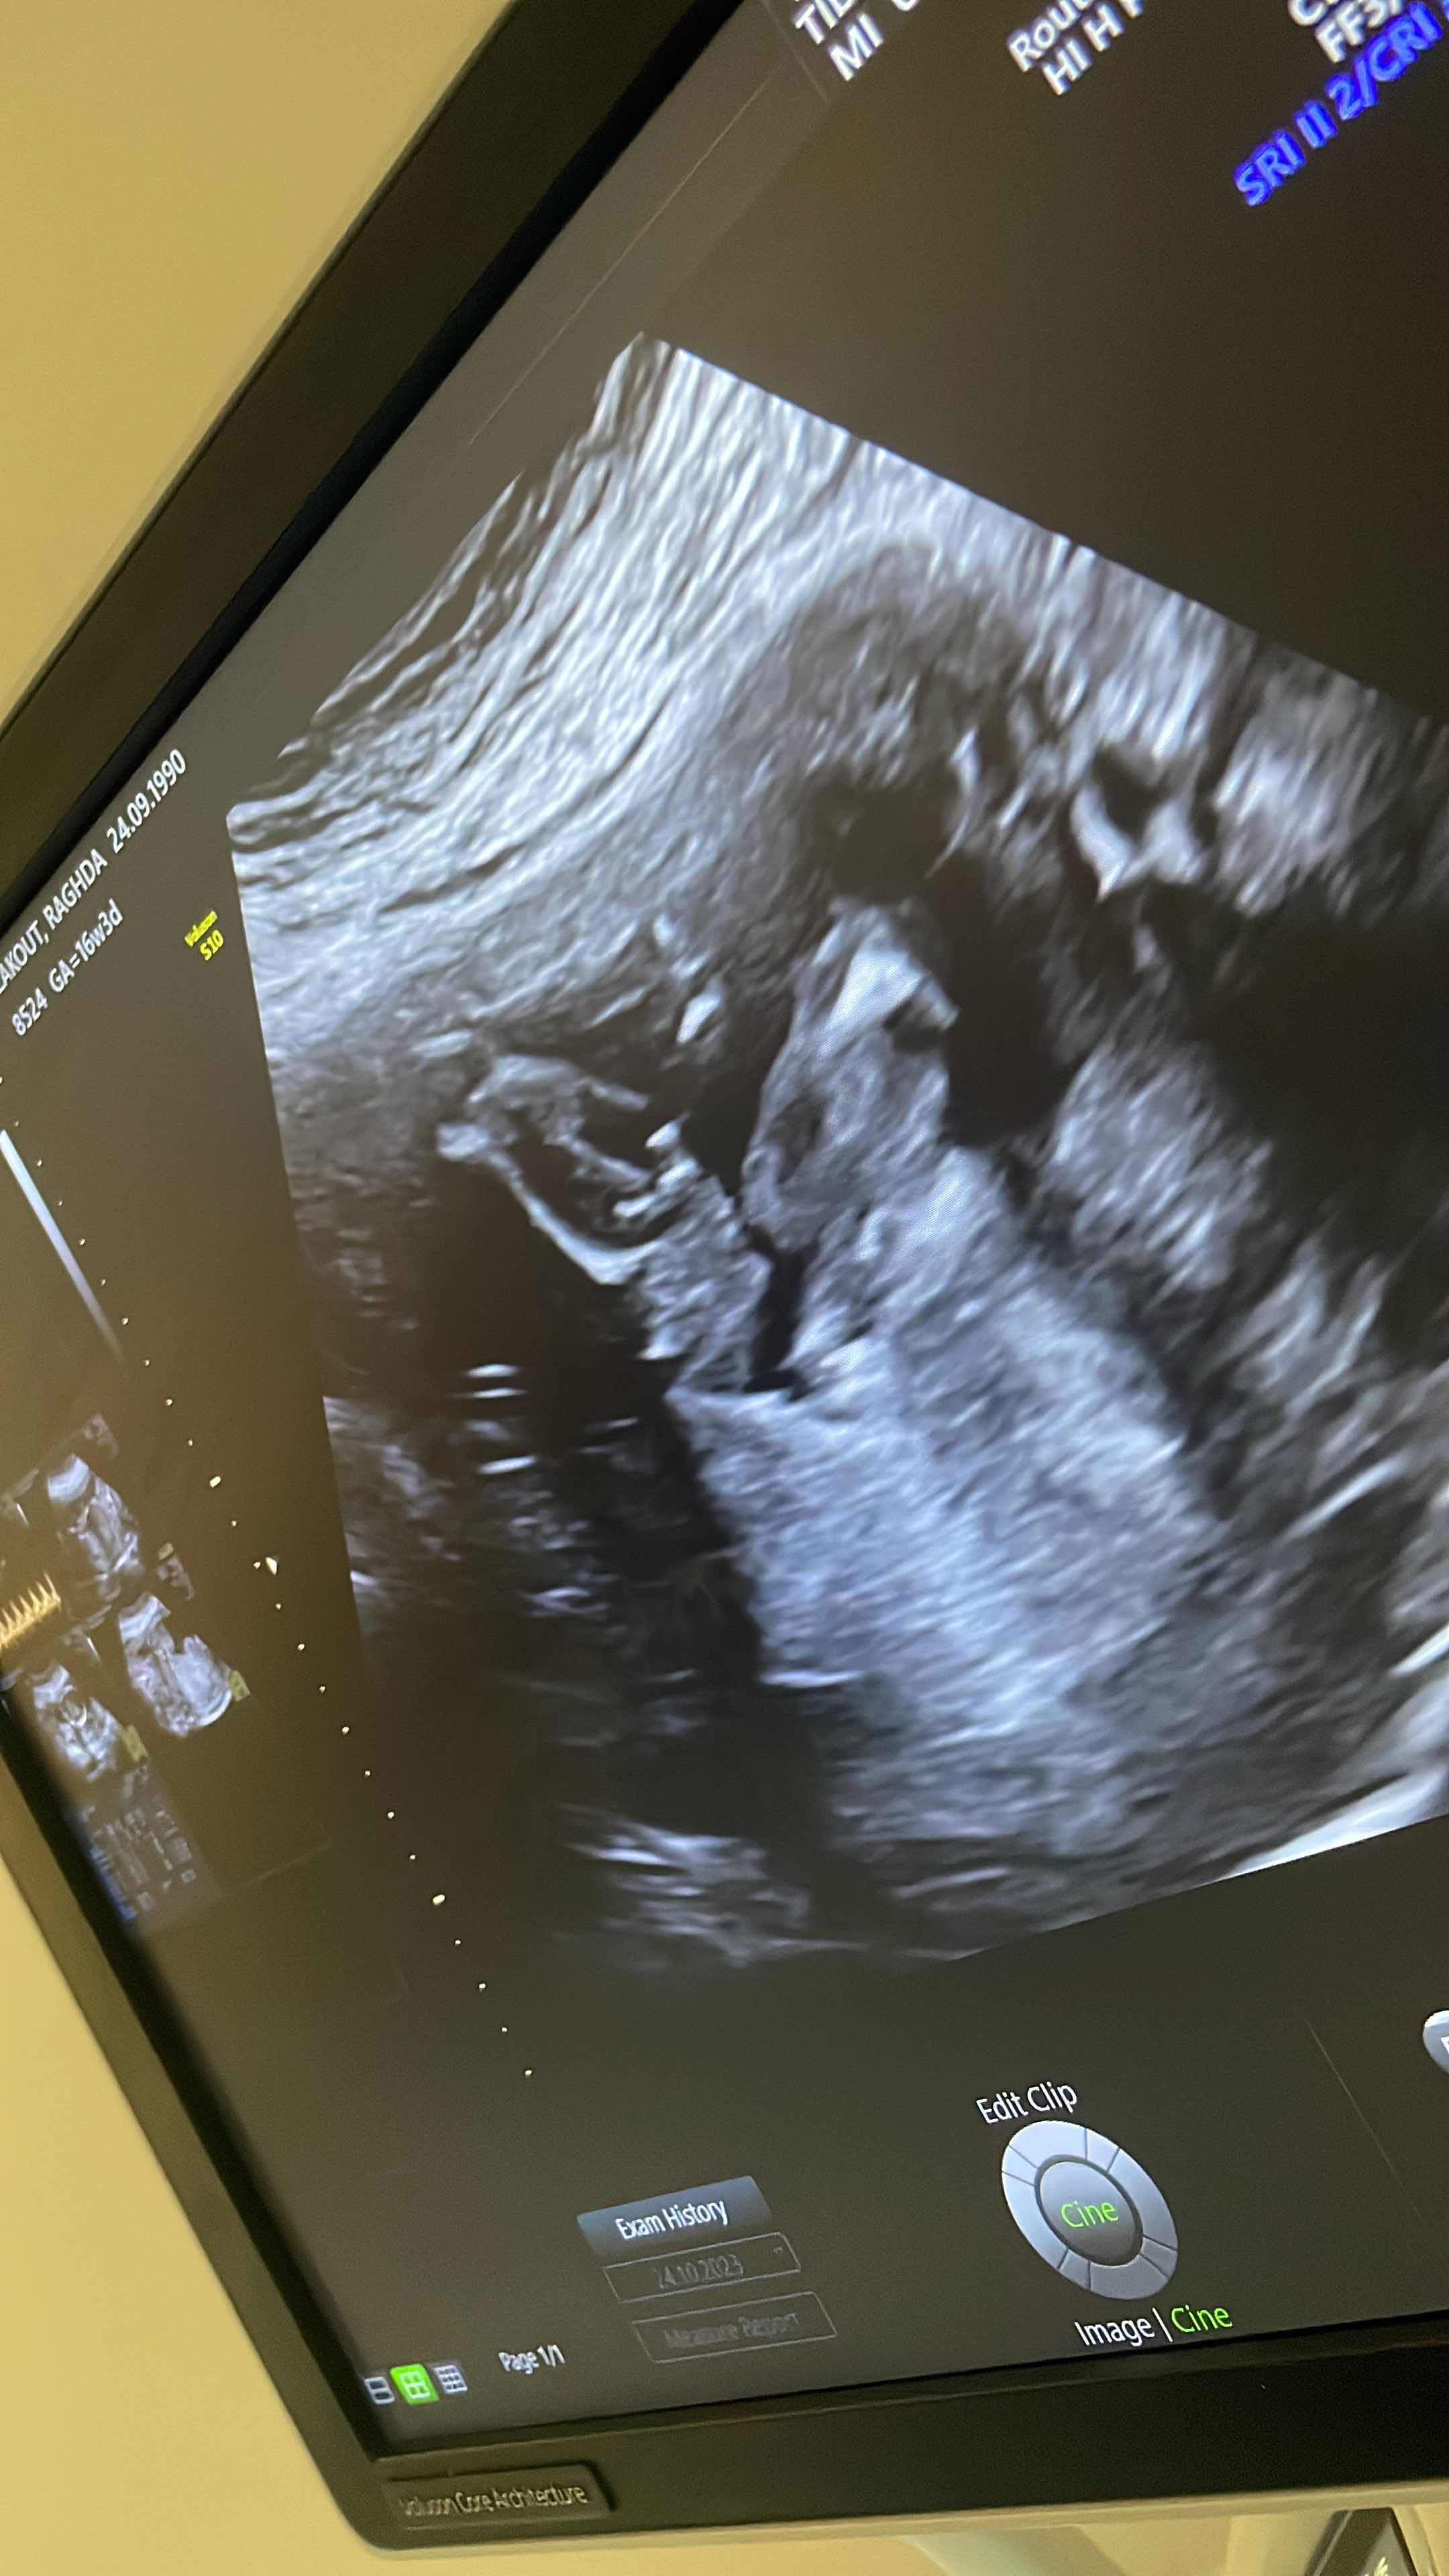

ثراءة صور سونار ذكر او انثى